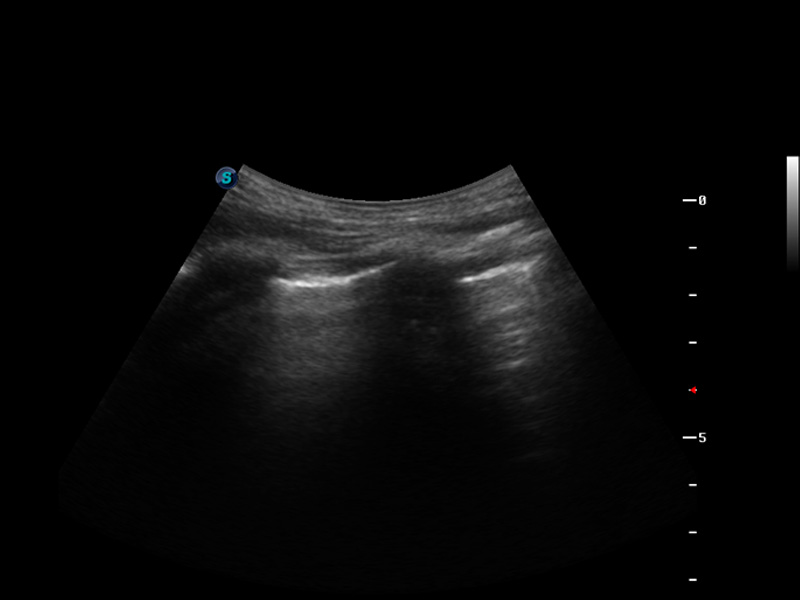

S9便携式彩色多普勒超声诊断仪是米兰官方网站研发的高端便携彩超设备,外观设计新颖、产品性能卓越。S9在便携超声领域采用了突破传统的触摸屏交互设计,并以先进的软件硬件技术和设计理念,为您带来清晰的图像质量、稳定的工作性能和便捷的操作体验。